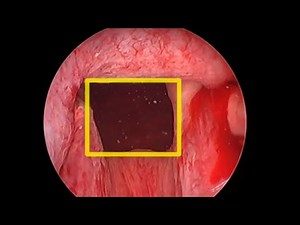

UroLift Box Technique

1.9K amharc

17 MFómh 2020

YouTube

Dr Rad